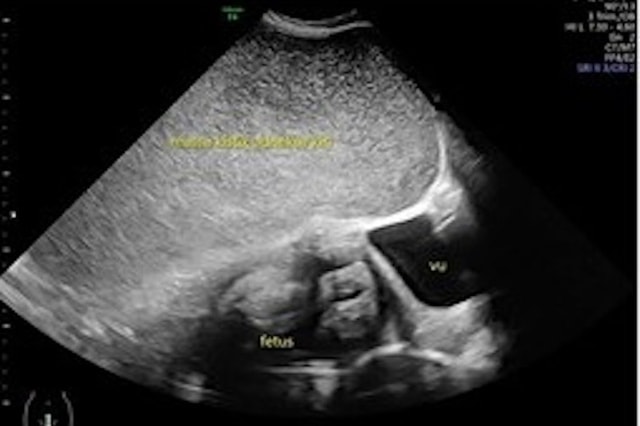

Người phụ nữ 26 tuổi mang thai ở tuần thứ 34 đã đi khám và phát hiện ra cô có một khối u nang rất lớn, đường kính 35cm, đang phát triển xung quanh em bé.

Cô đã siêu âm 6 tuần trước và phát hiện có u nang buồng trứng nhưng không phát hiện ra cho đến tam cá nguyệt thứ ba.

Sau lần khám bệnh thứ hai, các bác sĩ phát hiện thai nhi thực sự đã bắt đầu chậm phát triển – được cho là do u nang đẩy tử cung về phía bên phải bụng.

Bốn tuần sau, các bác sĩ đã phẫu thuật cho người mẹ. Họ phát hiện khối u nang nằm ở buồng trứng trái, chứa 11 lít dịch. Sau khi kiểm tra kỹ hơn, họ phát hiện nó có đường kính 35cm và được xác định là lành tính.

Trong khi đó, một ca sinh mổ đã được thực hiện để sinh em bé, và cậu bé nặng 2,2kg đã chào đời mà không có biến chứng nào.